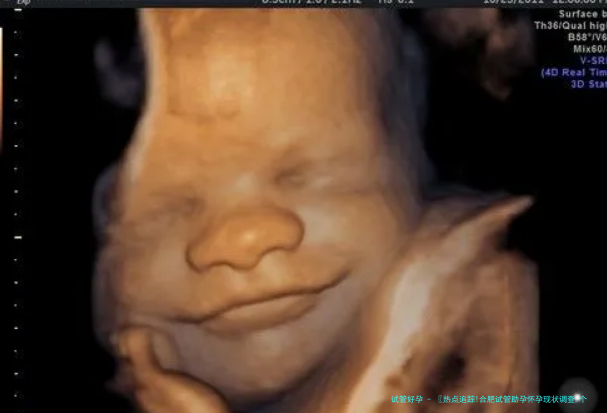

在合肥一家生殖中心门口,一双夫妇拿着检查报告相拥而泣——这就是他们第三回尝试试管移植,胚胎最终成功着床。这样的场景,在这座城市每日都在表演。2025年,合肥的辅助生殖技术已进入精细化、个性化时代,为很多家庭带来了新的期望 。

合肥的辅助生殖技术自2003年首个案例试管婴儿降生以来,已形成完善的诊疗网络。2025年,全市试管婴儿年周期数突破8000例,技术囊括一代到三代试管婴儿 。 这类快速增多背后,是技术精准化的不断提升。

随着辅助生育技术的不时创新和遍及,合肥试管婴儿范畴正变得更加规范和专业。以后,新技术有盼头进一步提升成功率,帮助更多家庭实现生育愿望 。 对于寻求助孕的家庭而言,结合自身心理先决条件与需求,抉择技术扎实、服务透明的机构,积极配合治疗方案,同时维系健康生活模式和良好心态,方能在这场生命接力中稳握胜算 。